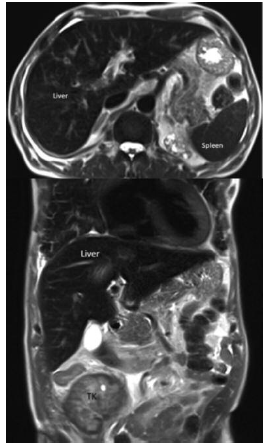

Renal function continued to deteriorate during the following week, requiring initiation of dialysis therapy. Blood and urine and pleural cultures were negative for bacteria, acid-fast bacilli, and fungi. Anti-human herpes virus 8 (HHV-8) antibody was positive, but serologic tests for CMV, BK virus, hepatitis B and C viruses, and human immuno-deficiency virus were negative. A noncontrast magnetic resonance image (MRI) of the abdomen showed a “bulky” transplanted kidney and multiple well-defined lesions of variable sizes in the liver and spleen (Figure 1).

Mycophenolate and tacrolimus were withdrawn. Prednisolone was continued, and sirolimus was added to prevent acute graft rejection. During the next 2 months, his general condition improved and he gained 4 kg of weight. Follow-up ultrasonography 3 months later showed complete resolution of hepatic lesions. Subsequent ultrasonography and MRI studies over the next 6 months confirmed complete resolution of Kaposi sarcoma lesions in the liver and spleen and progressive decreases in size and volume of kidney allograft (Figure 4). Despite radiologic regression of Kaposi sarcoma, renal transplant function did not recover. Repeat renal biopsy was not performed. Immunosuppression was gradually tapered off, and no signs of graft intolerance syndrome were seen. Sixteen months after the diagnosis of Kaposi sarcoma, the patient is in complete remission, although he is dependent on dialysis.

Figure 1. Abdominal Magnetic Resonance Image Showing Multiple Kaposi Sarcoma Lesions in Liver and Spleen and “Bulky” Transplanted Kidney (TK)

Figure 4. Follow-Up Abdominal Magnetic Resonance Image Showing Complete Resolution of Kaposi Sarcoma Lesions in Liver and Spleen and Decrease in Size of Transplanted Kidney (TK)